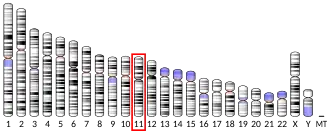

Genetics

Allelic variants:

- A-241G

- C132T, G423A, T765C, C939T, C957T, and G1101A[25]

- Cys311Ser

- -141C insertion/deletion[26] The polymorphisms have been investigated with respect to association with schizophrenia.[27]

Some researchers have previously associated the polymorphism Taq 1A (rs1800497) to the DRD2 gene. However, the polymorphism resides in exon 8 of the ANKK1 gene.[28] DRD2 TaqIA polymorphism has been reported to be associated with an increased risk for developing motor fluctuations but not hallucinations in Parkinson's disease.[29][30] A splice variant in Dopamine receptor D2(rs1076560) was found to be associated with limb truncal tardive dyskinesia and diminished expression factor of Positive and Negative Syndrome Scale (PANSS) in schizophrenia subjects.[31]